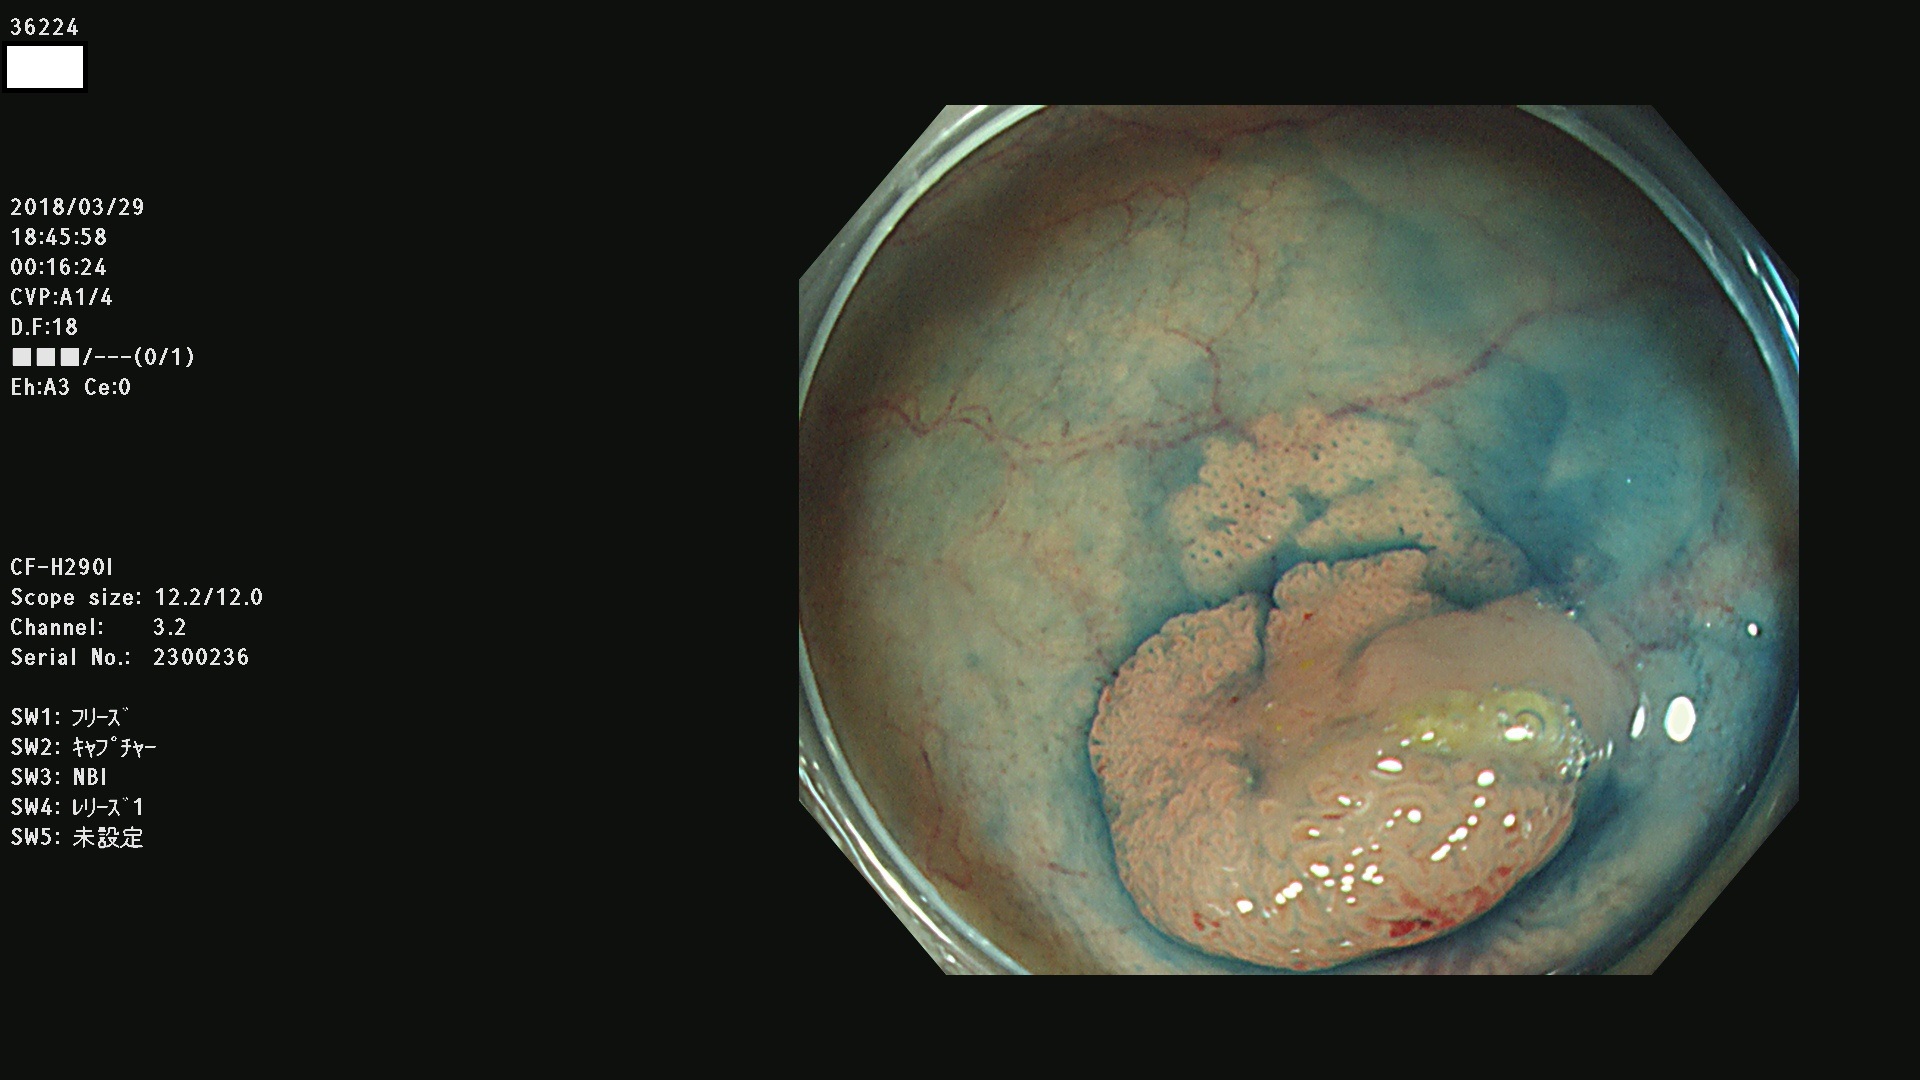

36201 36202 36203 36205 36207 36209 36210 36212 36213 36214 36215 36217 36220 36221 36222 36224 36225 36226 36227 36229 36230 36231 36232 36235 36236 36238 36240 36243 36244 36246 36247(SSAPのみ。SPS) 36248 36249 36251 36252 36253 36254 36255 36256 36257 36258 36259 36261 36262 36264 36265 36267 36269 36270 36272 36274 36275 36276 36279 36280 36281 36283 36285 36288 36289 36291 36292 36295 36296 36297 36299

発見困難で危険性の高い平坦型病変(上記100名より抽出)